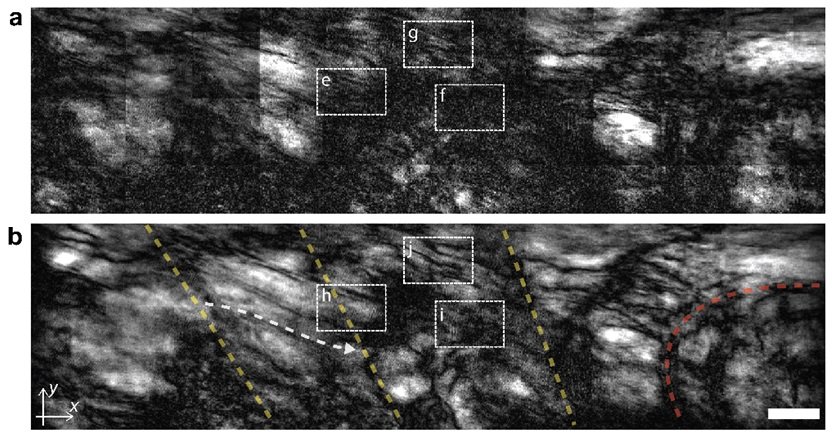

일반 광학 현미경(a)과 공간 게이팅 현미경(b)을 이용해 제브라피시 내부를 들여다 보았다. 공간 게이팅 현미경을 사용하면 기존에는 관찰하기 어려웠던 근육중격(노란 점선), 근육-뼈 접합부(붉은 점선) 등의 미세 구조를 관찰할 수 있다. (출처 : IBS)

▲ 일반 광학 현미경(a)과 공간 게이팅 현미경(b)을 이용해 제브라피시 내부를 들여다 보았다. 공간 게이팅 현미경을 사용하면 기존에는 관찰하기 어려웠던 근육중격(노란 점선), 근육-뼈 접합부(붉은 점선) 등의 미세 구조를 관찰할 수 있다. (출처 : IBS)